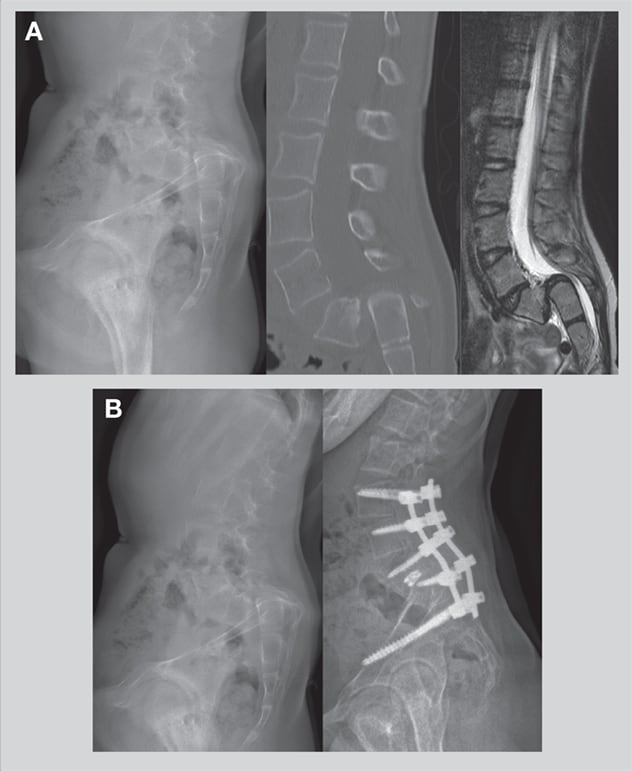

A. X-ray, CT and MRI demonstrate grade 5 spondylolisthesis of L5 on the sacrum in a 12-year-old girl. B. On the left, a preoperative X-ray shows misalignment. On the right, a postoperative X-ray shows nearly normal alignment.